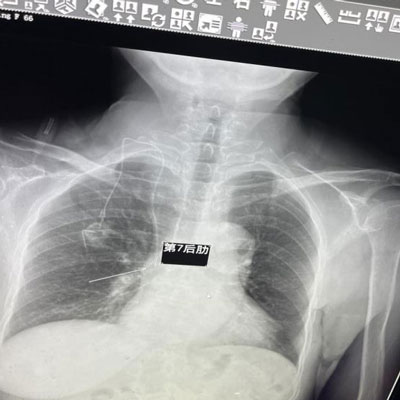

手术完成 术后X线确认

接受此次静脉输液港植入术的是一名66岁乳腺癌患者。因病情需要进行8个周期术后化疗,反复静脉穿刺带来的痛苦与不便让人难以忍受。与患者家属充分沟通后,普外/胸外科团队决定为患者实施静脉输液港植入术。11月5日上午,主治医师张文和静脉治疗专科护士张宇卓了解了患者的病情及身体状况后,为可能出现的麻醉应激意外、术中大出血、静脉血栓栓塞等多重风险做了充分准备,在局部麻醉下,一小时内顺利完成静脉输液港植入术,将“ 穿刺困难 " 变为简单快捷的 " 一针到位 "。静脉输液港植入术后,患者无任何不适,各项治疗均顺利进行。